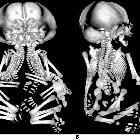

Classification

Conjoined twins are classified according to the most prominent site of interconnection

Ventral union

- thoracopagus: thorax, commonest site (~70% )

- ischiopagus: pelvis ~5%

Radiographic assessment